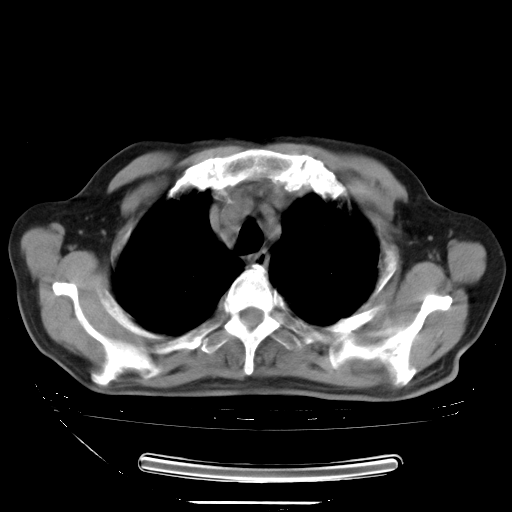

今天复查肺部CT,发现双肺广泛磨玻璃样改变。所以我把3月19日和5月9日相隔50天的肺部CT上传。请大家会诊。

2009年3月19日肺部CT片。

2009年3月19日肺部CT

大致读了系列胸部CT:纵隔窗无明显异常,肺窗:从4、27至今:主要是双肺中下野外带可见毛玻璃样改变,目前处于急性肺泡炎阶段,至于原因考虑1、结替组织或胶原血管性疾病所致?2、恶性疾病如恶组在肺部所致的表现或细支气管肺泡癌?3、药物或其它原因如肺蛋白沉着症所致肺泡炎目前不太可能?总之,明天就去请我院的呼吸科、感染科、血液科和临免专家会诊哈。